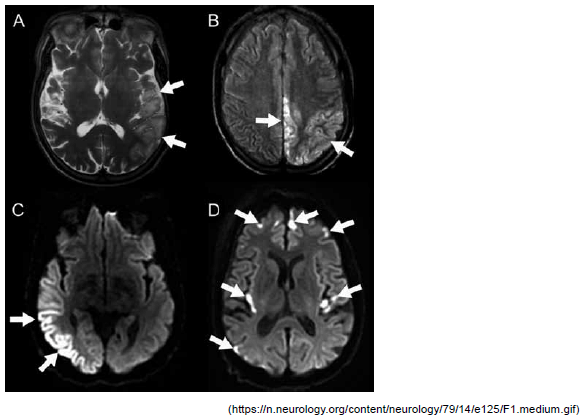

A imagem a seguir refere-se a um paciente masculino, 30 anos, com antecedentes de crises convulsivas, perda auditiva progressiva e diabetes mellitus tipo 1 e admitido com quadro sugestivo de ataque isquêmico transitório. Com base nesse exame, o exame complementar ideal para a confirmação da suspeita diagnóstica desse paciente, a ser coletado na emergência, é: